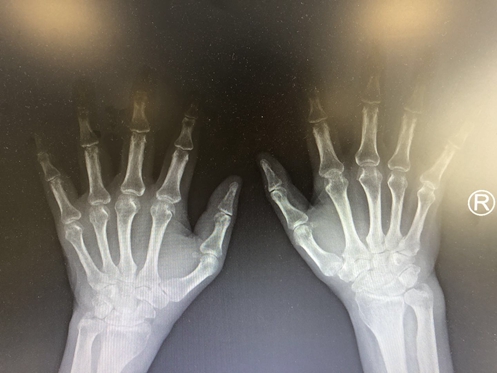

多关节间隙变窄,甚至关节半脱位